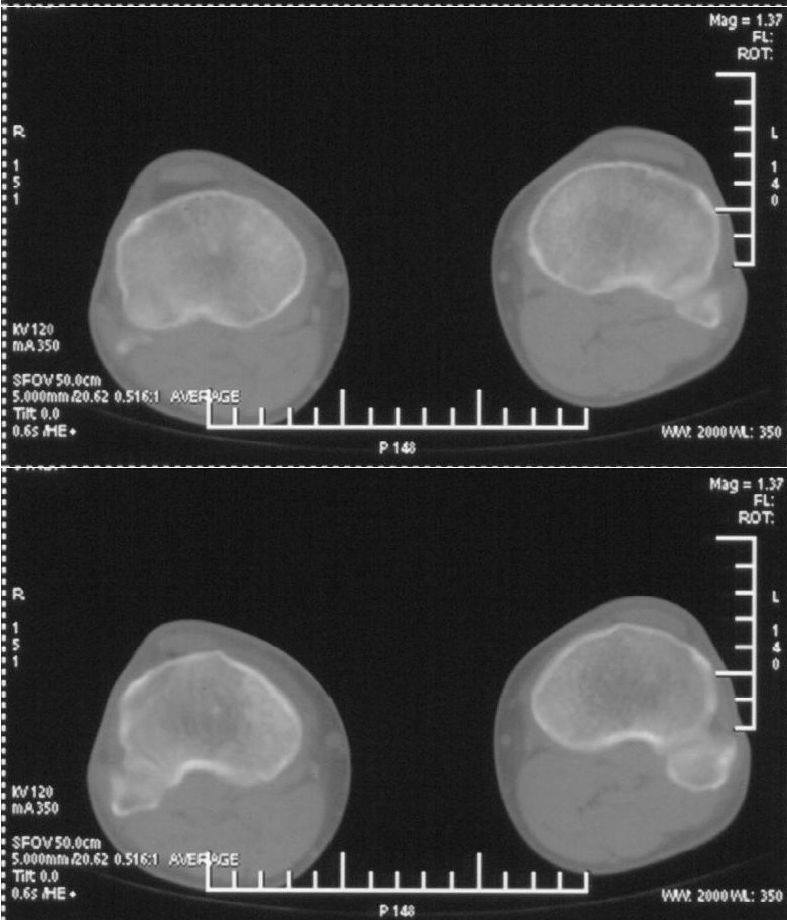

男,42岁。4个月前钢筋钝伤右侧小腿部,当时因无明显外伤,未引起重视。一周后因受伤腿部疼痛,发现肿胀,随后到当地医院进行检查(2008年4月16日)。因未发现骨质异常未引起重视,仅仅进行口服抗生素治疗处理。经过一段时间治疗但未见明显治疗效果在5月29日又进行x线检查,发现有胫骨密度上段密度增高,又进行抗炎治疗,仍未见效果。又在7月3日进行x线检查,仍然报告有胫骨上端密度增高,并建议ct检查。以下是相关检查结果:

髓腔密度呈絮状增高,胫骨上端内侧可见层状骨膜反应,考虑骨髓炎.

髓腔密度呈絮状增高,胫骨上端内侧可见层状骨膜反应,肌间隙模糊,考虑骨髓炎.

破坏、增生、骨膜反应,考虑骨髓炎

该患者到某三级医院进行会诊,并重新作了平片检查,认为畸形性行骨炎: